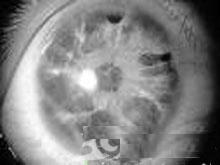

眼底1.前節炎症 輕度睫狀充血,角膜上皮水腫,有少量大小不等灰白色KP,大者呈羊脂狀KP,一般不超過25個多位於角膜下方或在房角小梁網,眼壓恢復正常後數天或數周消失。眼壓波動時可重新出現或不出現KP。房水中偶見浮游物,閃光弱陽性,前房不淺。房角開放,瞳孔輕度開大,對光反應存在,虹膜無前、後粘連。玻璃體無炎症細胞。

2.眼底 一般正常,但嚴重病例長期反覆發作,或每次發作持續時間長經常在高眼壓下可出現青光眼性視盤及視野改變。